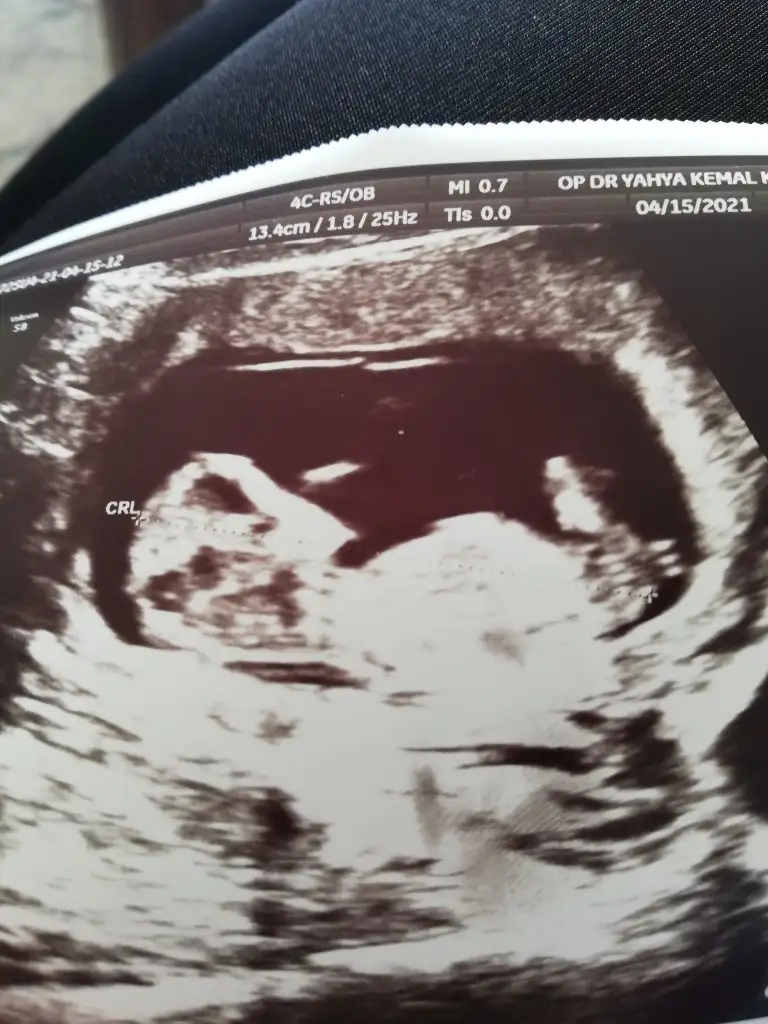

Tekrar USG paylaşın demiştiniz 12+5 günlük burada doktor bir tahmin yapmadı ne düşünüyorsunuz :)Ikra meyra

Kız görünüyorIkra meyra bana 11 haftalikken kız demiştiniz. Şimdi 12 haftalik kontrolden geldim. Doktor bacak arasini da çekti ama hiç tahminde bulunmadı. Sizce hala kız mı?

Bacak arasi dolu gibi ya herkes erkek dedi o yüzden. Bacak arası böyle olup yine kız olabiliyor muuKız görünüyor

Teşekkür ederim inşallah hayırlısıyla bakalım :)Kız görünüyor